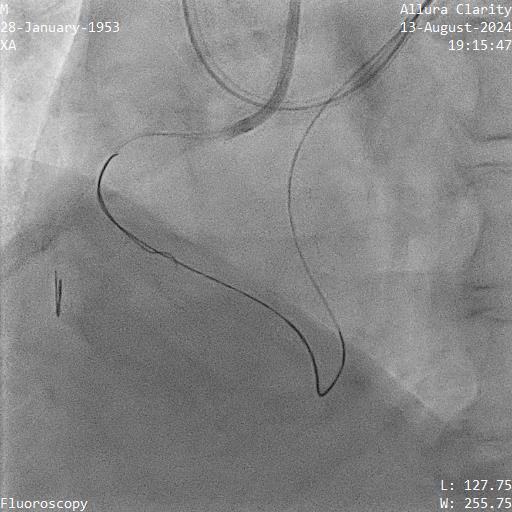

Right femoral and right radial arteries were punctured. A 7Fr EBU 3.5 guiding catheter (GC) was used to engage LMT. A 7Fr JR 4 GC was used for RCA CTO PCI. For antegrade preparation, a wire was delivered into right marginal artery. For antegrade proximal cap puncture, a Finecross microcatheter (MC) and Fielder XTR was used to wire into mid RCA CTO, but XTR fail to advance further. For retrograde approach, a CorsairPro ES (150 cm) MC, SION and SUOH 03 wire were used for LAD septal wiring but failed. A Sion Black with 90 degree tip successfully negotiate the collateral and entered PDA. The distal cap was hard to puncture. UB3 was used to puncture the distal cap and managed to cross and externalized into antegrade GC. Attempt was made to advance retrograde MC but failed at the point of PDA/PLV bifurcation.

Next plan was using retrograde UB3 to tip in antegrade MC successfully. However, the antegrade MC crossed the CTO body but failed cross PDA despite anchoring balloon at marginal artery. Next, switched to antegrade, escalated the antegrade wire to GAIA Next2 and using retrograde wire as a marker to facilitate antegrade wiring. Fortunately, the GAIA Next 2 managed to entered PLV. IVUS confirmed wire in true lumen after predilatation. The PDA was wired using CRUSADE MC to keep wire access for PDA and PLV.Distal RCA-PDA stented with everolimus eluting stent (EES) 2.5x32mm, mid RCA EES 3.5x32mm, and ostial RCA EES 4.0x24mm, post dilated NC 3.0x15mm, and 4.0x15mm balloon.